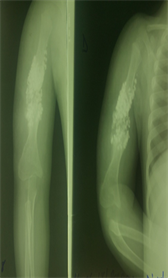

The second stage consisted of the explantation of the spacer (Figure 3) and the put on a non-vascularized fibula of 8 cm, taken from the homolateral leg by open procedure.

The surgical specimen was taken from patient on dorsal supine with a cushion under the buttock and under the pneumatic tourniquet. The intended osteotomy site was 6 centimeters from the fibula (Figure 2).

Figure 2. Site of osteotomy of fibula.